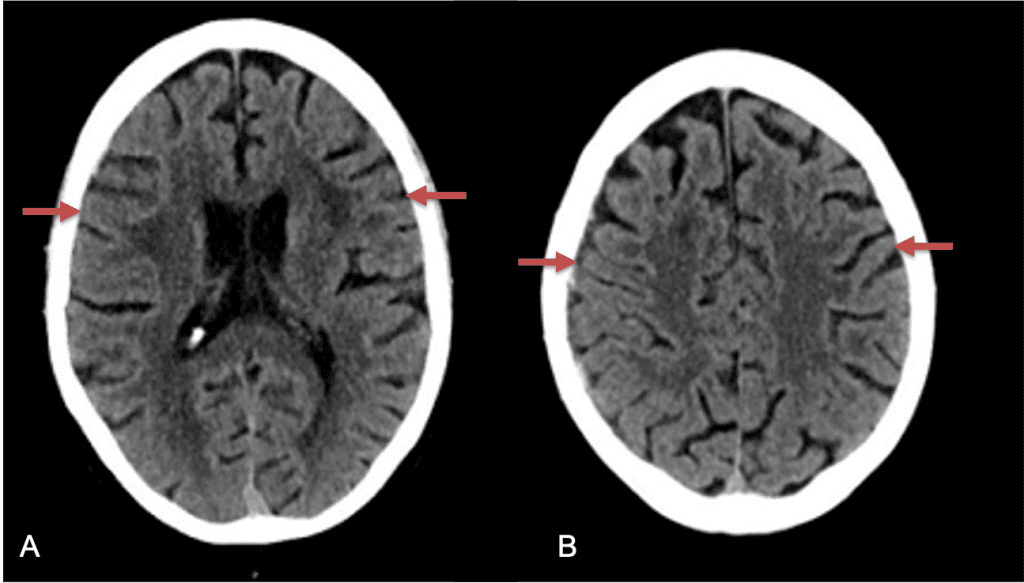

A woman in her 80s developed mild dizziness and headache following incidental trauma working in her garage one day. She presented several weeks later to the ER and was diagnosed with bilateral subdural hematomas, which were initially managed with observation, low dose Decadron, considering the mildness of symptoms, advanced age, and history of CLL with thrombocyptopenia (<100k). Over the next 4 weeks, the collections remained relatively stable with evidence of slight growth (10 to 12 mm thickness, and 2 mm right to left shift) on NCT (Figure 1. A and B).

Figure 1. A) 6 weeks post mild trauma B) 4 weeks post mild trauma demonstrates stable subacute subdural collections with mild growth and sulcal effacement.

CT follow-up at 1 week demonstrates early resorption. 2 weeks post MMA embolization, resolution of the left subdural collection with new small thin acute hemorrhage in an otherwise stable right subdural collection is observed (Figure 3. A and B).

Figure 3. A) 1 week post MMA embolization demonstrating decreasing thickness bilaterally B) 2 weeks post MMA demonstrates resolution on left, with small new acute component on right with overall decreased thickness.

Clinically, the patient improved over the few weeks with the occasional transient twinge of a headache, but resolution of dizziness. Follow-up CT at 10 weeks demonstrated complete resolution of the bilateral subdural hematomas with our patient completely asymptomatic and back to all of her activities of daily living. Considering her history of thrombocytopenia and CLL, we will continue to monitor her into the future and are excited about her progress and recovery. (Figure 4. A and B)

Figure 4. A and B) – 10 weeks following embolization demonstrates complete resolution of bilateral collections both acute and chronic.